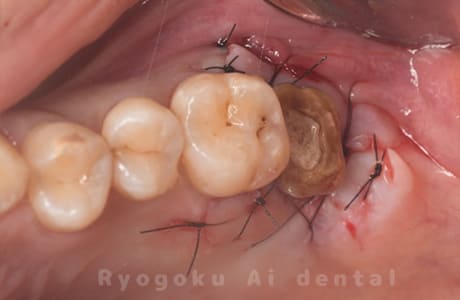

- 原因

- 左上6番重度カリエス

- 治療内容

- クラウンレングスニング

- 治療費用

- 44,000円(根管治療、補綴は別途費用)

他院で抜歯と判断された歯です。クラウンレングスニングを行い、保存を試みました。現在も問題なく被せ物が入り、使用できてます。

<リスク・副作用>

手術後は痛み、腫れ、痺れ、青あざなどの副作用が生じます。痛みは痛み止めを処方しますが、腫れ、青あざは1週間程度生じる場合があります。また、部位によっては神経の走行が複雑で、痺れが残り、長期的にお薬を処方する場合があります。